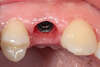

Trois mois après la pose d’implant, on dépose la vis de cicatrisation et l’on peut sceller la couronne définitive. Vue de la connectique interne de l’implant (photo 1)

Prémolaire maxillaire fracturée (photo 1) non conservable en l'état car le trait de fracture se situe sous le niveau de l'os de soutien. L'extraction est réalisée en urgence pour soulager la douleur et 2 mois plus tard un implant dentaire remplaçant la racine est posé. On attends ensuite 3 mois que l'implant s'intègre à l'os puis un pilier est transvissé sur l'implant (photo 2) et une couronne céramique est scellée sur ce pilier qui ne sera évidement plus visible (photo3).